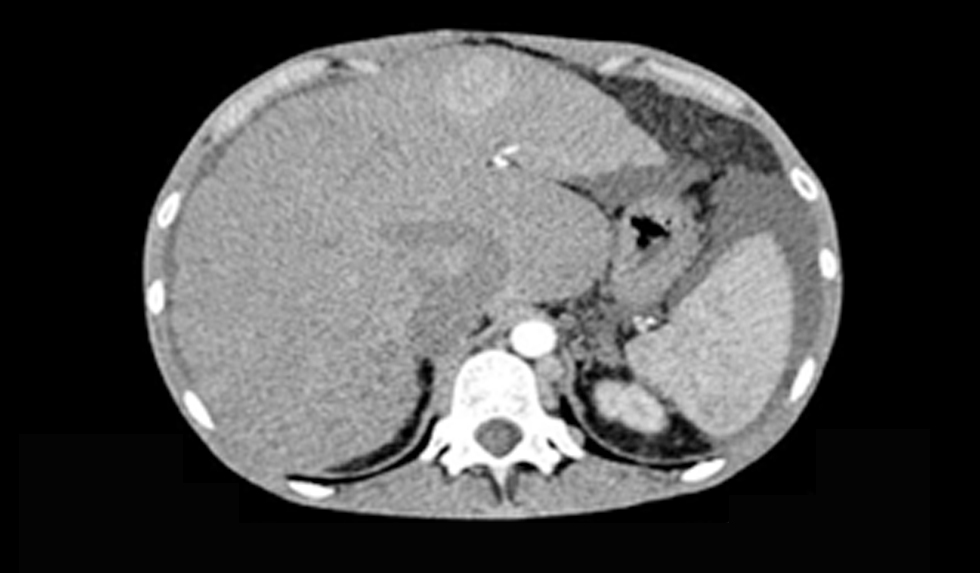

Our patient received continue theraphy with dabigratan etexilat (Pradaxa) 9 month and she performed CT scan every 3 month. In june 2018 CT scan evaluation described moderate ascities due to DIPS thrombosis (figs. 2, 3, 4).

Figure 2 - CT scan 1.5 mm arterial - Direct Intrahepatic Portocaval Shunt thrombosis (June 2018)